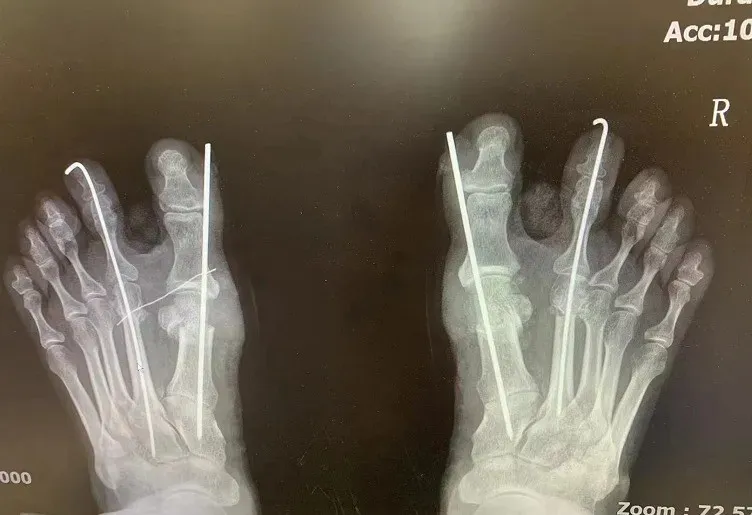

上图为术前术后对比图

术前术后X光片对比图

微创所需设备和手术器械:C形臂X线机或微型C形臂X线机、足踝微创动力系统,裂钻,磨头微创复位器械,微型骨膜剥离子,骨科手术常规操作器械,克氏针。